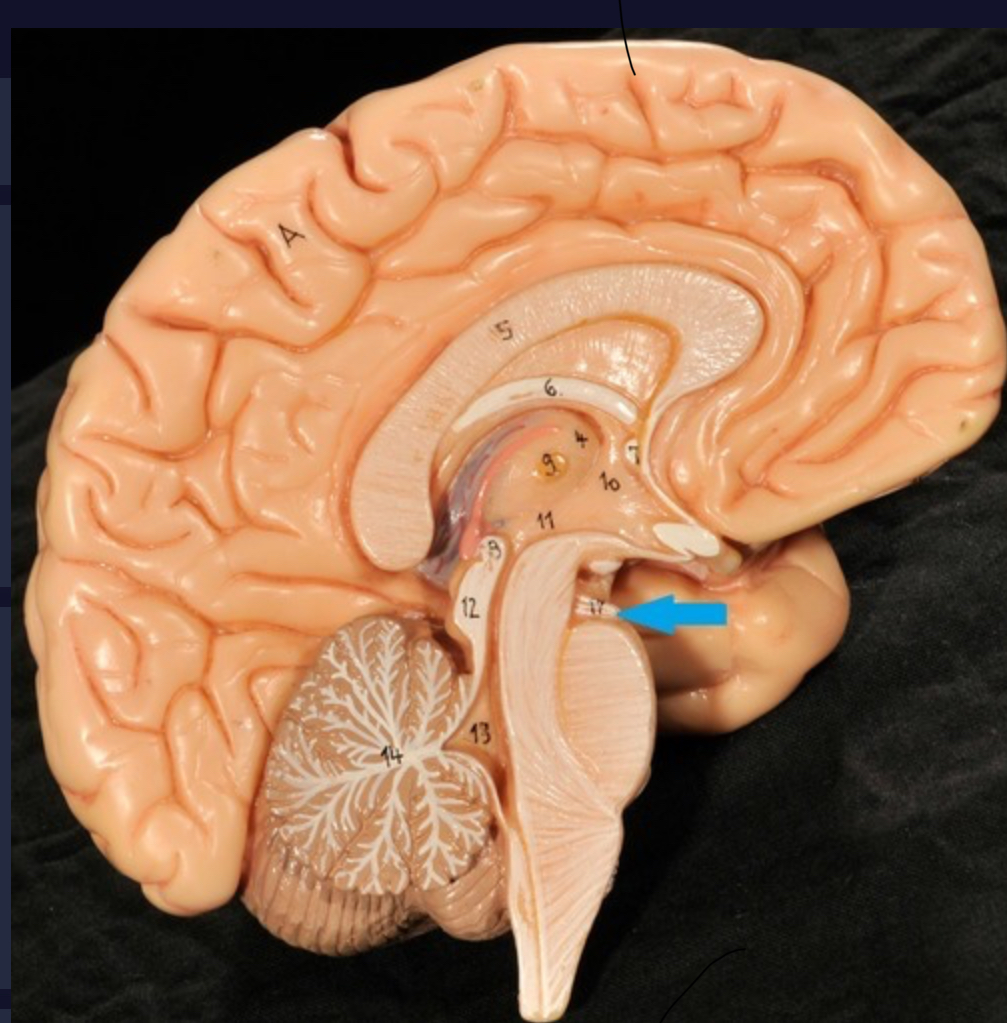

Corpus callosum

Diencephalon

Thalamus

3rd ventricle

Hypothalamus

Epithalamus (pink line)

Brain stem

Pons

Medulla oblongata

Choroid plexus of 3rd ventricle

Cerebral aqueduct (midrain)

4th ventricle

central canal